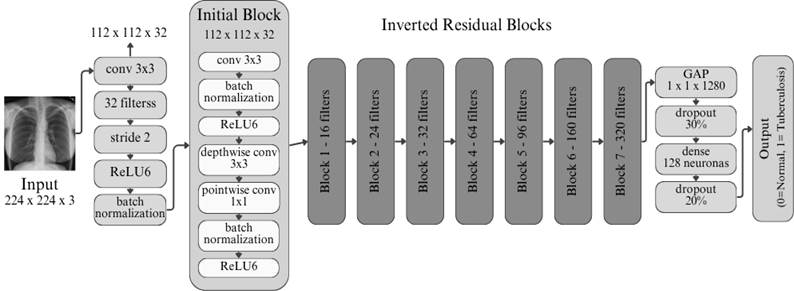

· MobileNetv2

Figura 4. Arquitectura de MobileNetv2.

Elaboración: Los autores.

Por otro lado, como se muestra en la Figura 4, MobileNetv2 es una arquitectura optimizada para dispositivos móviles y entornos con recursos computacionales limitados, basada en bloques convolucionales invertidos con conexiones residuales lineales. Esta configuración permite reducir significativamente el número de parámetros y operaciones, manteniendo un desempeño competitivo (Hadi y Ali, 2021).

En la arquitectura, el modelo inicia con una capa de entrada de imágenes (224x224x3), seguida de una capa de convolución 3x3 con stride 2, que reduce las dimensiones. Esta primera etapa está acompañada de Batch Normalization y activación ReLU6, optimizando la extracción inicial de características, para posteriormente, organizarse en una serie de Bloques de Inversión Residual (Inverted Residual Blocks), que aprovechan convoluciones depthwise y pointwise para maximizar la eficiencia. El flujo culmina en una capa de Global Average Pooling, seguida de una capa densa de 128 neuronas (ReLU), una capa Dropout para regularización y una salida Sigmoide que permite la clasificación binaria (0 = Normal, 1 = Tuberculosis).